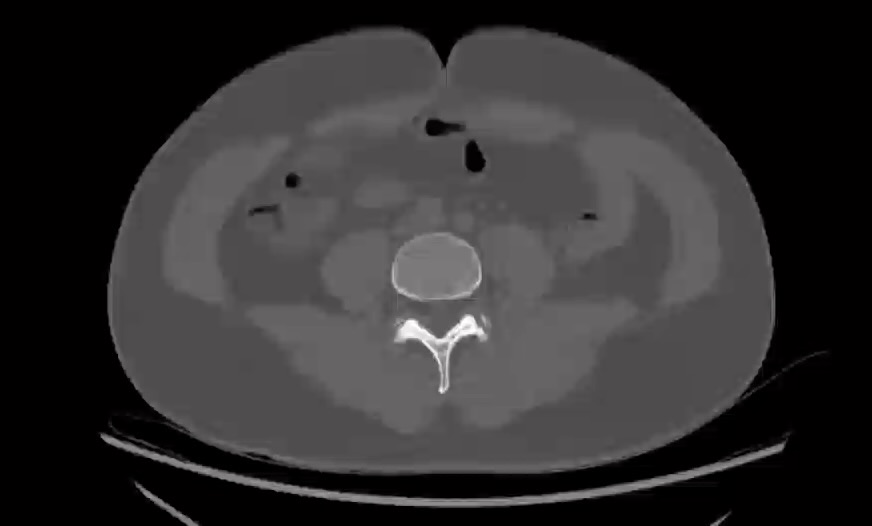

病例【骨肌】左侧髂骨占位?腰部外伤后腰痛5小时,男,39岁。

【患者信息】:男,39岁。

【主诉】:腰部外伤后腰痛5小时。

【现病史及既往史】:无手术史。

【检查】